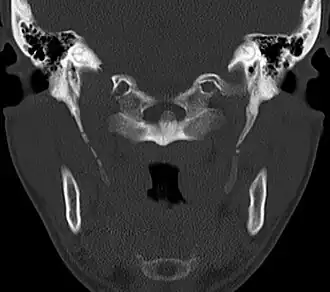

CT scan, coronal section showing bilateral extended styloid process and stylohyoid ligament ossification (incidental finding) -

Diagnosis is suspected when a patient presents with the symptoms of the classic form of "Eagle syndrome" e.g. unilateral neck pain, sore throat or tinnitus. Sometimes the tip of the styloid process is palpable in the back of the throat. The diagnosis of the vascular type is more difficult and requires an expert opinion. One should have a high level of suspicion when neurological symptoms occur upon head rotation. Symptoms tend to be worsened on bimanual palpation of the styloid through the tonsillar bed. They may be relieved by infiltration of lidocaine into the tonsillar bed. Because of the proximity of several large vascular structures in this area this procedure should not be considered to be risk free.

Imaging is important and is diagnostic. Visualizing the styloid process on a CT scan with 3D reconstruction is the suggested imaging technique.[13] The enlarged styloid may be visible on an orthopantogram or a lateral soft tissue X ray of the neck.